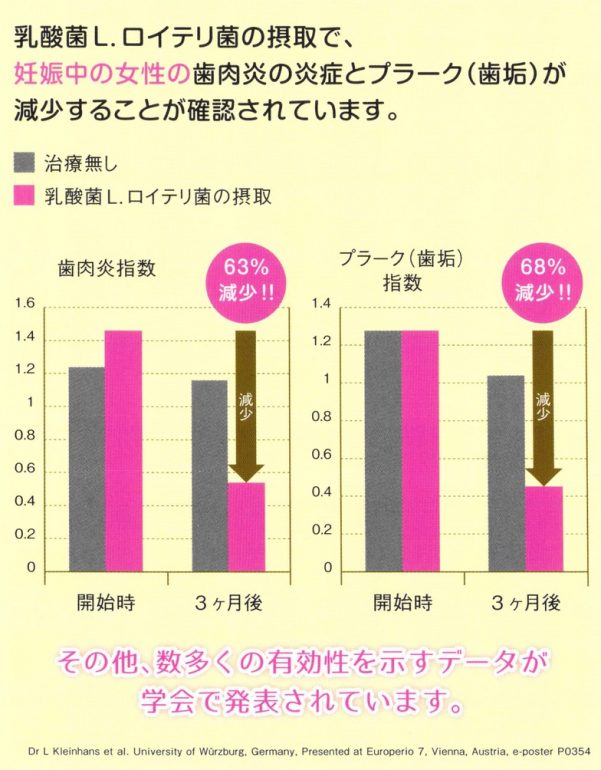

通常の歯科治療やメンテナンスに加え、母乳由来の乳酸菌であるロイテリ菌を摂取していただくだけで、口腔内の病原菌の減少、胃や腸内環境の改善、授乳中では母乳の質の改善も認められいます

歯周病の原因菌を減少させる

歯周病菌は約90%減少します。歯科医院での専門ケアと組み合わせることで効果があります。

妊娠中や授乳中の方

歯周病菌の殺菌・抑制

歯周病菌は低体重児や早産のリスクを高めるため妊娠中は歯周病菌の殺菌が重要です。